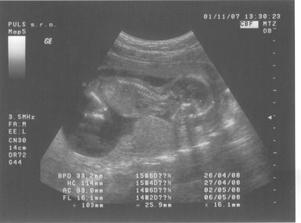

17.8.2007 jsem doma dělala těhu testík a byly 2 //. Poslední kontrola byla 4.9.2007 - 7.tt, velikost miminka 9,6 mm a už bilo srdíčko.Další kontrolu máme 2.10.2007 ... už jsem zvědavá... 2.10.jsem přinesla moč, dostali jsme průkazku a na utz byl vidět pěkný macíček 7,36 cm, čekala jsem o něco málo menší 🙂. Do alba jsem přidala fotečky z utz, ale nejdou popsat - na první - je vidět hlavička, jedna ručička si mne očičko a druhá podpírá hlavičku, okolo tělíčka jsou žebírka, na druhé - je vidět zadeček s nohama křížem ... to je pohodička a na třetí - je celé miminko s nožkama nahoře ..pěkně odpočívá. Jinak bylo vše vpořádku, další kontrola bude 1.11.2007-kontrola, mimís měřil přes 14,5 cm a vážil 189 g. Při kontrole pásl koníčky 🙂. Konečně mi vzali krev asi už na vícero vyšetření najednou. Další návštěvu máme 27.11. ... kontrola byla velmi rychlá, miminek zase pekně pózoval a rozesmíval pana doktora i mě. Chvíli se dívalo nahoru, pak se kokulo na nás z očí do očí. Všechny testy dopadly dobře - triple test i rozbor krve, tak si jen přeju, aby to tak bylo i nadále. Příští kontrolu 3.1.2008 už nebude vidět miminko na ultrazvuku celé, protože už bude moc velké, tak to už se budu dívat jen na jednotlivé části tělíčka 🙂.3.1.2008 byla kontrola ještě rychlejší 🙂, pan doktor zkontroloval srdíčko, jestli ťuká. Při odchodu jsem dostala žádanku na odběry k těhotenské cukrovce, bylo to jen male píchnutí do prstu, s vypitím glukósy v černém čaji. Příští kontrola je 29.1.2008, jsem zvědavá jak dlouho budu ještě moct chodit do práce.Miminko už se má pěkně k světu, už i tatínka kope přes bříško 🙂). Další kontroly probíhaly většinou vpořádku, akorát během února se panu doktorovi zdálo mimi malé, tak jsme čekali jestli doroste, a povedlo se. Doktor t ozdůvodnil tak, že miminka nemusí růst podle průměru, ale podle toho jak se jim chce, což je samozřejmě logické. Nechtěla jsem vedět pohlaví, spíš se těším na překvapení u porodu. Do práce jsem chodila, co to nejdýl šlo, všechno bylo vpořádku. Jen mi při posledním odběru zjistili pozitivní protilátky, tak mi je hlídají a na endokrinologii mi předepsali užívání jodu. Na další kontrolu půjdeme 4.4. do porodnice v Podolí. Kontrol v Podolí bylo ještě několik. V den termínu porodu jsem šla na delší procházku, večer upekla buchty a navařila a ono nic. Poslíčci mě strašili celkem dva týdny, ale vždycky to přešlo. Nakonec jsme museli jít na vyvolání 2.5.2008.